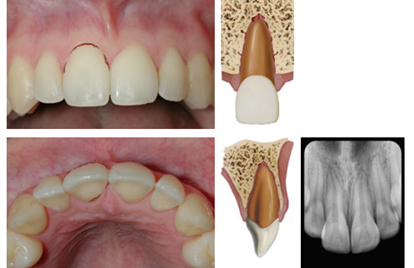

dx lateral luxation

A

Displaced usually in palatal/lingual or labial direction

High metallic/ankylotic sound

Usually mobile

Sensibility tests will likely give a lack of response except for teeth with minor displacements.

* The test is important in assessing risk of healing complications. A positive result at the initial examination indicates a reduced risk of future pulp necrosis.

Occlusal, PA and 2 eccentric exposures from diff horizontal angulations

* Widened PA ligament space